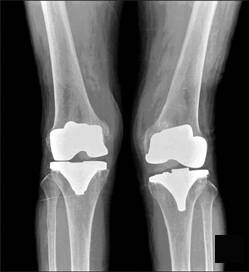

Protesi ginocchio

Protesi di ginocchio con dolore persistente

Vi può essere un dolore persistente dopo un intervento di protesi al ginocchio per diverse cause, alcune di difficile diagnosi. E’ possibile però avere un dolore persistente anche senza una complicazione evidente della protesi di ginocchio

Oggi ragionevolmente possiamo affermare che le moderne protesi di ginocchio dovrebbero funzionare per un tempo compreso dai 10 ai 20 anni nel 90% dei pazienti.

Tuttavia, fino ad un quarto dei pazienti sottoposti ad un intervento di protesi di ginocchio si dichiarano insoddisfatti dell'intervento con dolore al ginocchio con protesi.